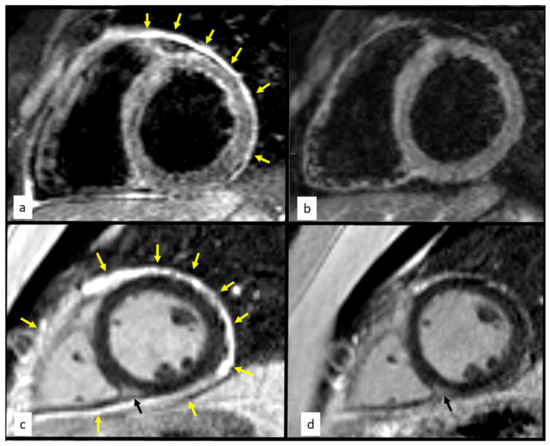

Fijolek, J.; Gawryluk, D.; Piotrowska-Kownacka, D.; Ozieranski, K.; Wojnicz, R.; Wiatr, E. Chest Pain of Atypical Cause in a Young Man. Diagnostics 2022, 12, 1881. https://doi.org/10.3390/diagnostics12081881